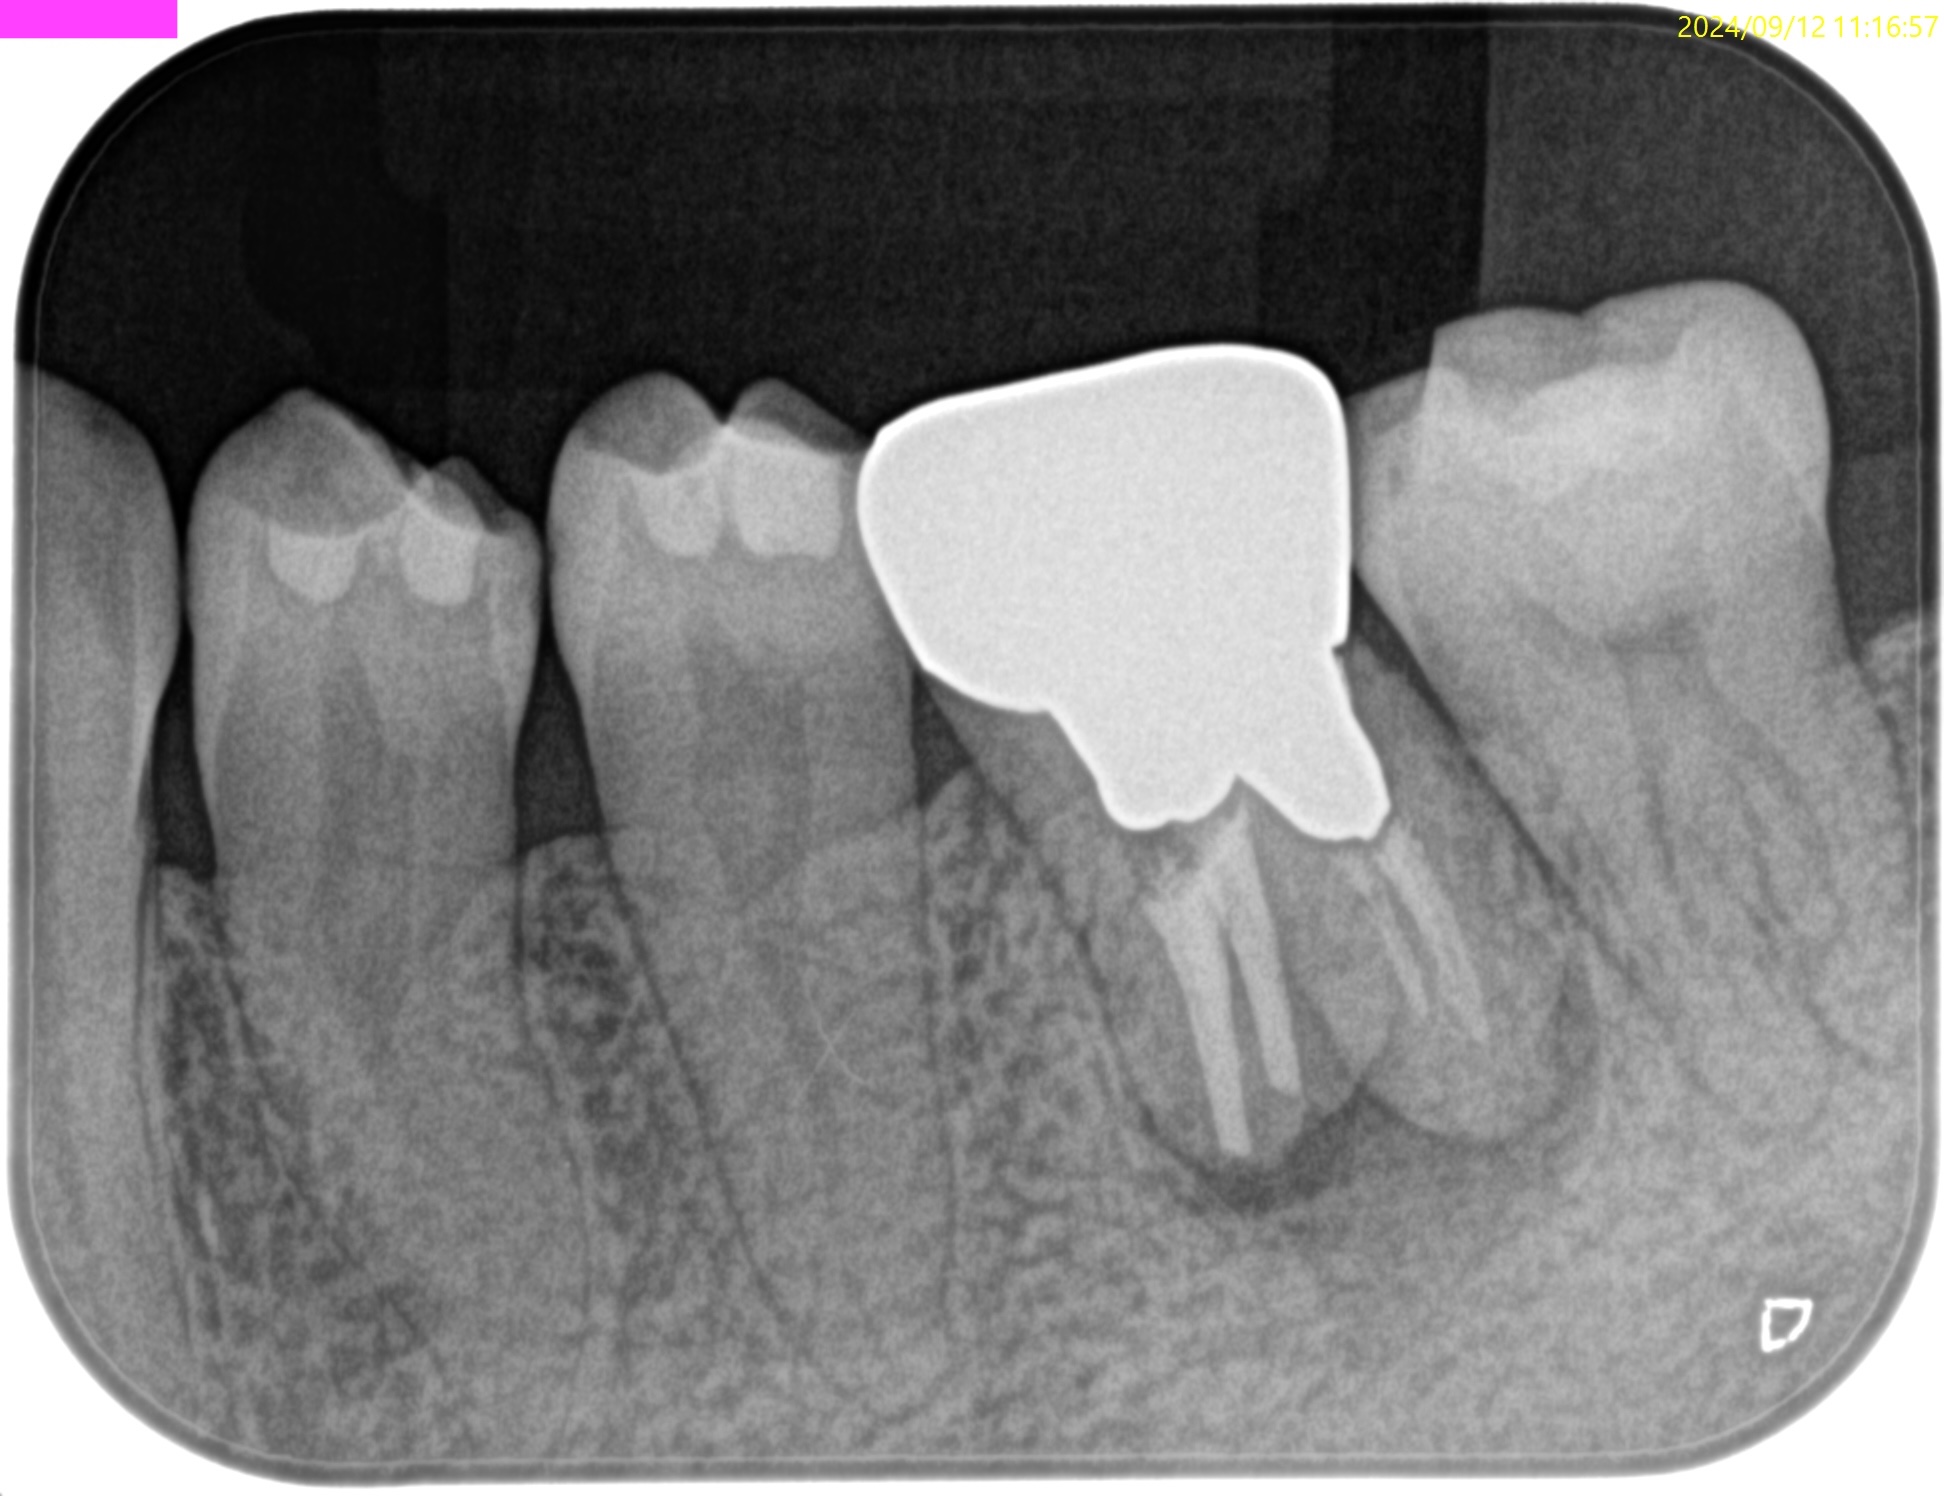

PA(2024.9.12)

Pre-op Endo test(2024.9.12)

頬側と舌側の2箇所にSinus tractがあった。

この時点で外科が決定的だ。

Pre-op Endo Diagnosis(2024.9.12)

Pulp Dx: Previously treated

Periapical dx: Chronic apical abscess

Recommended tx: Apicoectomy